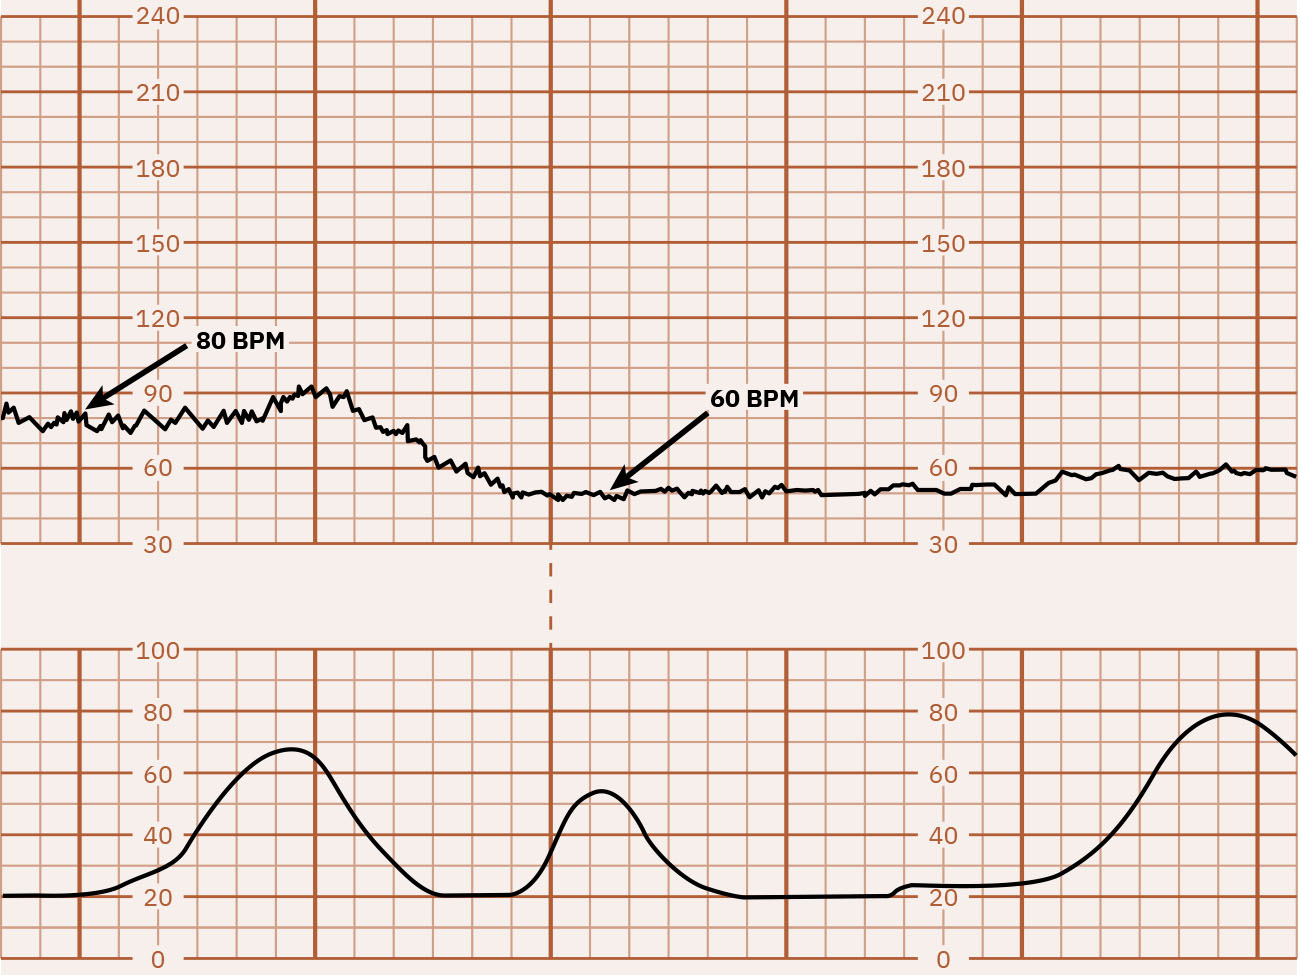

• 기저선: 주요 주기성 변화와 현저한 변이도를 제외한 10분 평균 FHR로, 보통 5-bpm 간격으로 기록합니다. 빈맥은 10분 이상 160 bpm 초과, 서맥은 10분 이상 110 bpm 미만입니다.

60 bpm 범위로 저하되는 기저선 서맥을 보여주는 FHR 추적 예시 Illustration reference: OpenStax Maternal-Newborn Nursing Ch.16.1.

• 기저선을 확인하고 빈맥(10분 이상 >160) 또는 서맥(10분 이상 <110)을 식별합니다.

• 기저선 서맥에서는 모체(저혈압/마취 영향, 대사 원인, 일부 약물, 주요 산과 응급, 모체 맥박 오독 가능)와 태아(아두/제대 압박, 저산소증, 선천 전도 이상) 기여 요인을 검토합니다.

• 서맥 우려에서는 즉시 체위 변경과 IV 수액 지지를 시작하면서 지속 기저선 서맥과 지속 감퇴를 신속히 구분합니다.